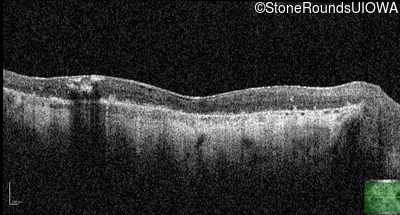

AR Stargardt Disease (IIA)

OD

OS

Light Perception sc

Show more

OCT Stack

AR Stargardt Disease

ABCA4

Gln636Stop CAG>TAG

His1406 del1caC

AR